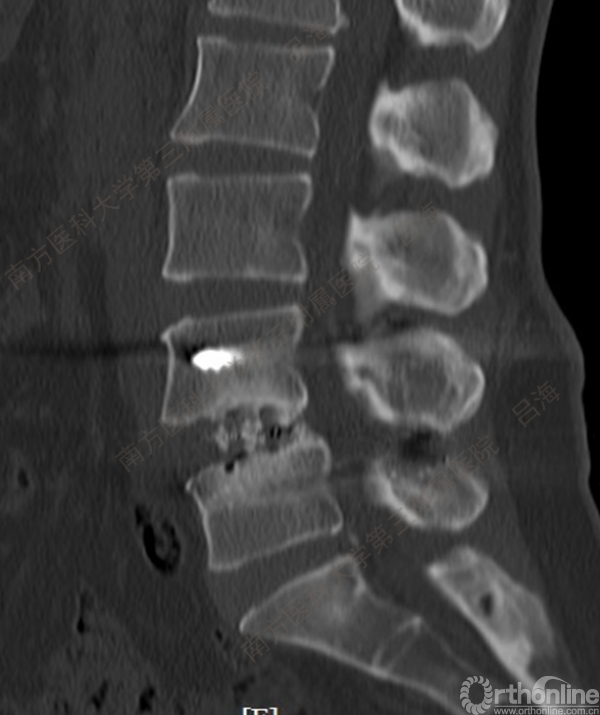

随着社会老龄化进程加快,胸腰椎退行性病变的治疗已经成为脊柱学术界的一个热点话题。MIS-TLIF手术可以治疗多种不同的胸腰椎退行性疾病,南方医科大学第三附属医院吕海教授结合病例为我们一一展示了该术式在治疗不同胸腰椎疾病时的具体手术过程。